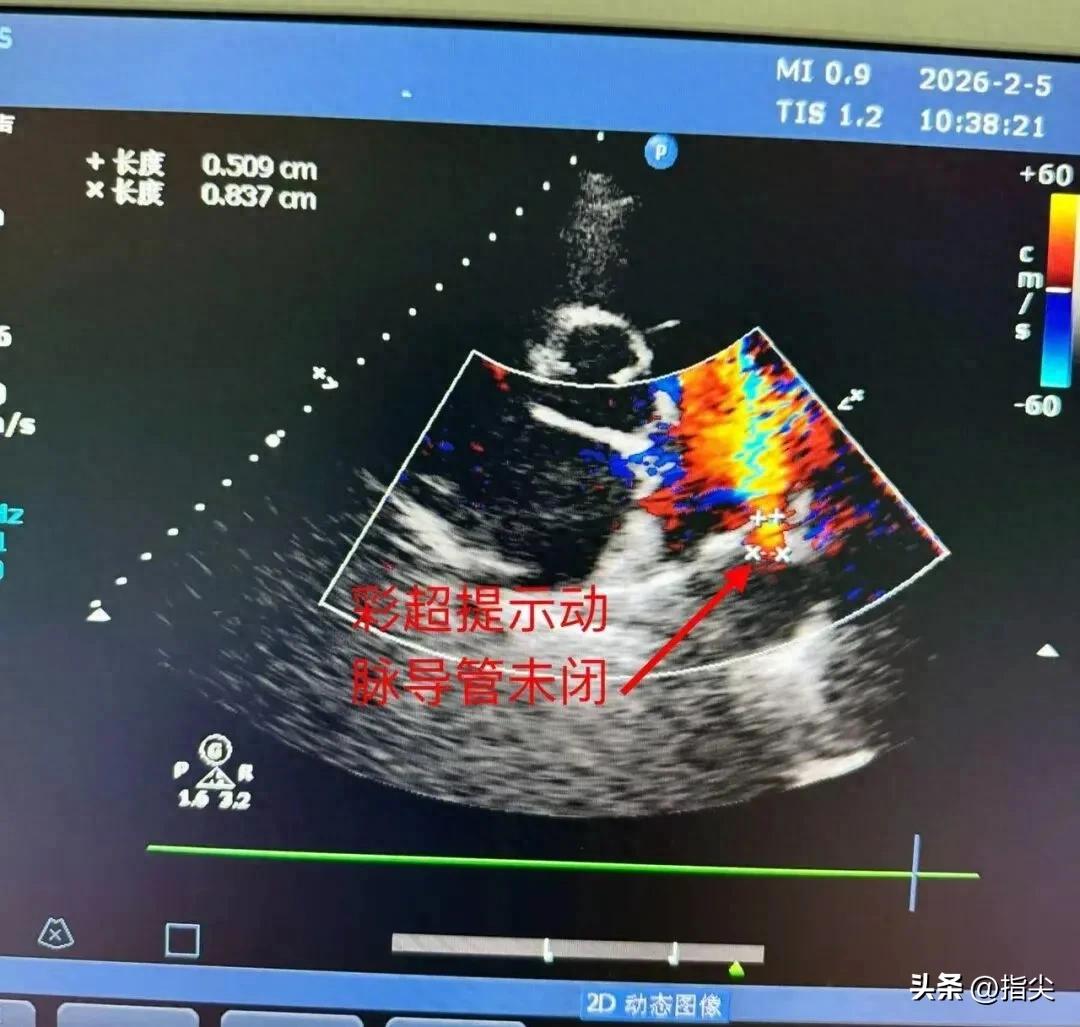

此次接受手术的两位患者,其中一位动脉导管未闭患者,因长期动脉分流导致左心扩大,活动后气促,心功能不全;另一位卵圆孔未闭患者,长期头痛、头晕,伴有晕厥,心源性卒中。两例患者术前均经该科心脏影像团队进行了精确的超声心动图等评估,明确了手术指征。

动脉导管未闭是胎儿期主动脉与肺动脉间的动脉导管,出生后未正常闭合而遗留的先天性血管畸形,是儿童常见的先天性心脏病之一。动脉导管细小的患者可能无症状,1岁前能自然闭合,未闭合者可通过手术治疗。成人动脉导管未闭可能导致主动脉血液持续分流至肺动脉,增加肺循环血量和心脏负担,长期可能引发左心增大、肺动脉高压、心力衰竭等严重并发症。